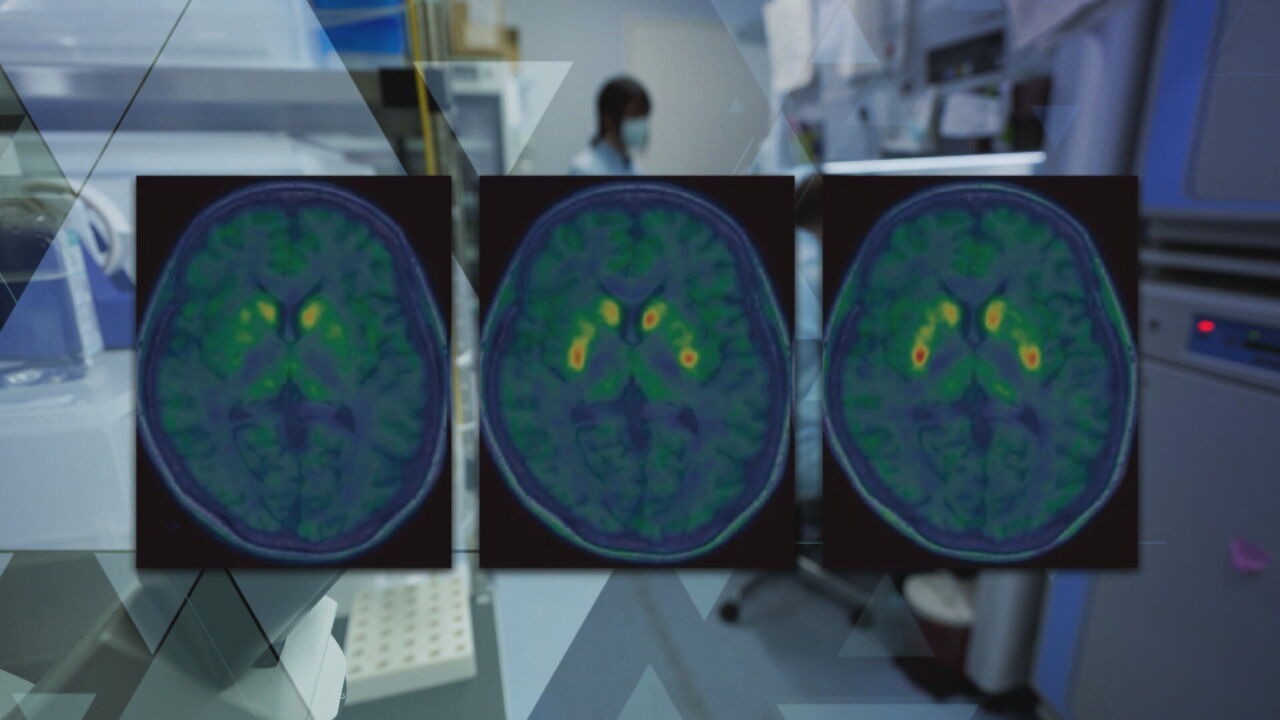

O objetivo é que elas passem a produzir dopamina de forma contínua, compensando a perda dos neurônios originais. Exames de imagem feitos após o transplante mostraram um aumento significativo da dopamina em áreas específicas do cérebro. Os sete paciente que receberam o transplante têm entre 50 e 70 anos.

Então, as transformamos em células neurônios produtores de dopamina. Usamos dez milhões de células", explica Jun Takahashi, responsável pela condução do estudo. Pesquisa no Japão usa terapia celular e apresenta resultados inéditos no tratamento do Parkinson — Foto: Reprodução/Fantástico